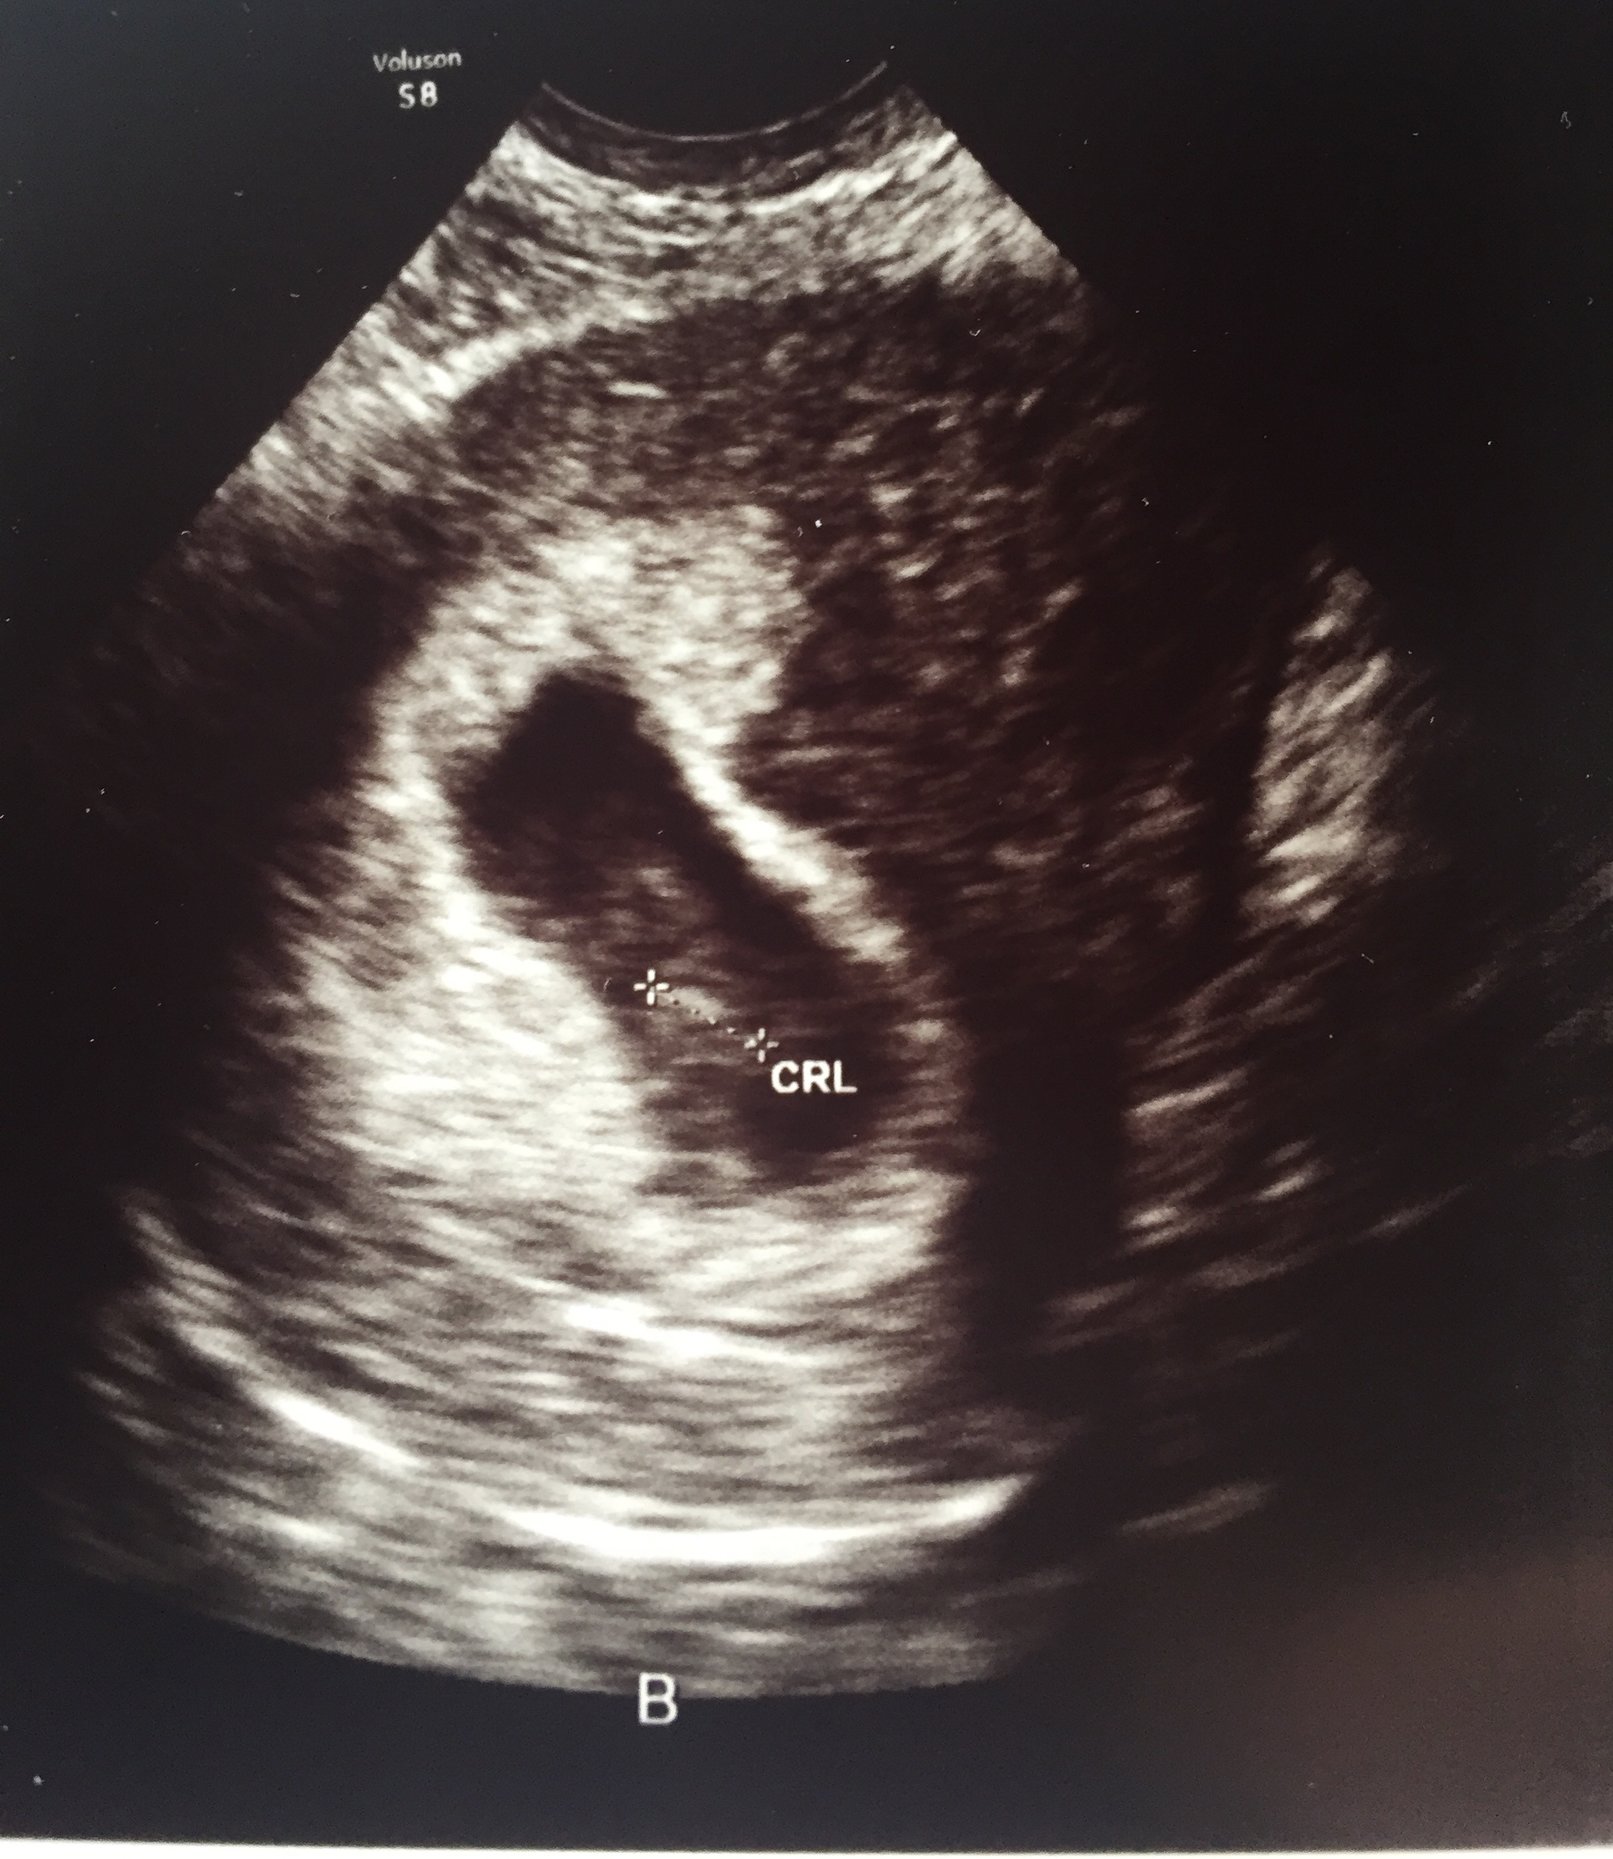

• @EmilyE13 thought your u/s was tomorrow but must be getting my dates wrong!  Congrats on your two little beans! They are beautiful and so happy you could hear the heartbeat.

• @EmilyE13 that's amazing!! Congrats! Thabks for sharing the beautifl pictures.

• @emilye13 your precious babies!!!!! I'm so glad to hear they are healthy little peanuts! <3

@EmilyE13. What beautiful sonogram pics so happy for you good luck on the healthy process of your pregnancy